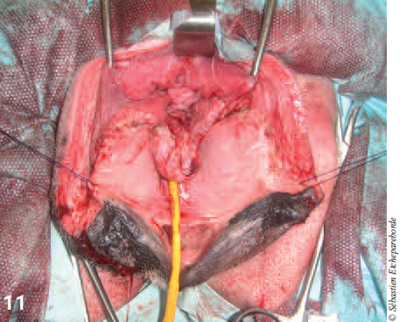

photo 11

Photo 11 – Tout le vagin a été retiré et ne reste que le vestibule avec le méat urinaire.

Après ressection, le vestibule est refermée par un surjet simple et des sutures résorbables puis l’épisiotomie est refermée en 3 plans (photos 11 à 14). La masse a été envoyée au laboratoire pour analyse histologique.